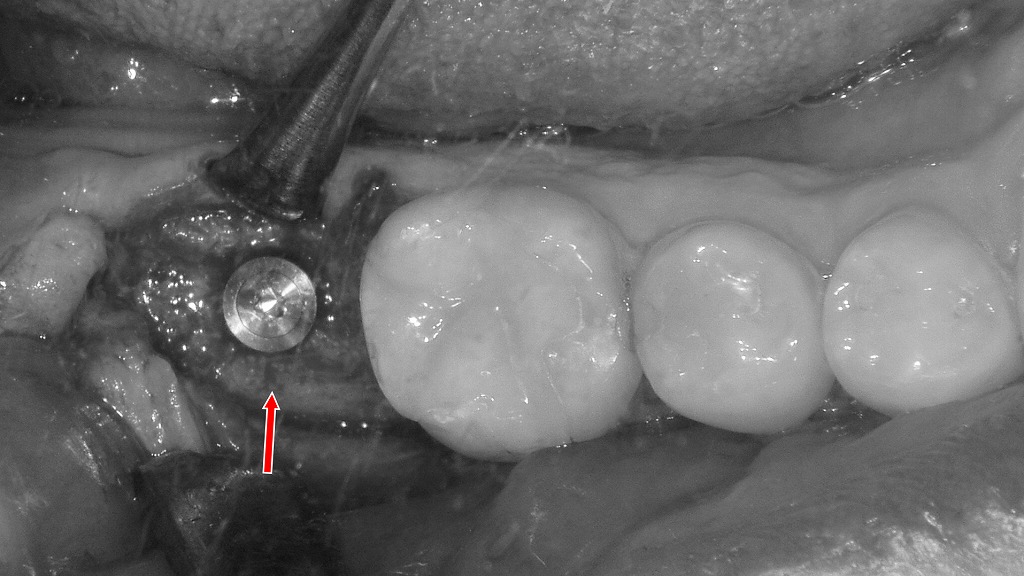

抜歯後にインプラントを選択した症例(下顎7番)

下顎7番に歯根破折(垂直破折)が認められ、歯の保存が困難と判断されたため抜歯を選択しました。本症例では抜歯後、欠損部にインプラントを埋入し、噛む機能の回復を図っています。